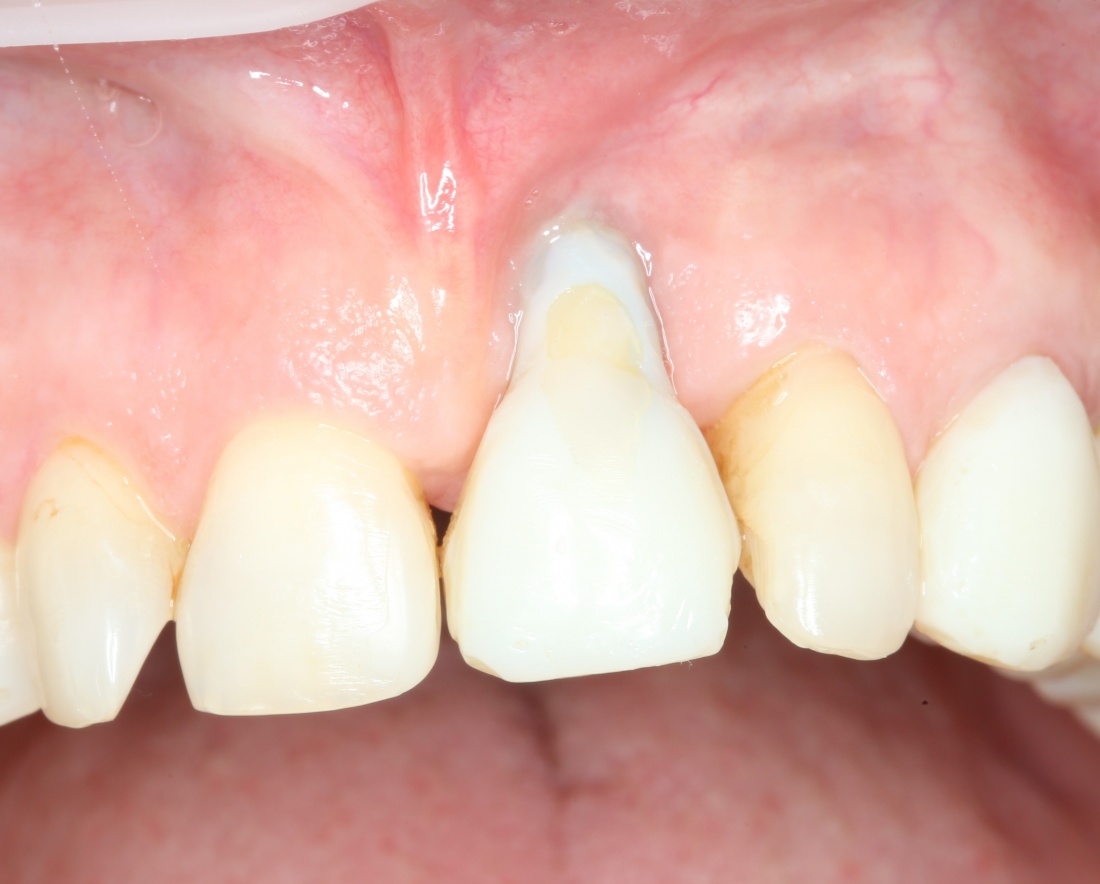

Можно пожертвовать первичной стабильностью в угоду правильного положения. И ни в коем случае нельзя пытаться добиваться первичной стабильности в ущерб правильному положению. Иначе это приводит вот к таким проблемам:

А история тут была такая: доктор изначально планировал немедленную имплантацию с немедленной нагрузкой, но вдруг стабильности импланта оказалось недостаточно — и он решил закрутить его поглубже. Результат…. собственно, вы видите результат.